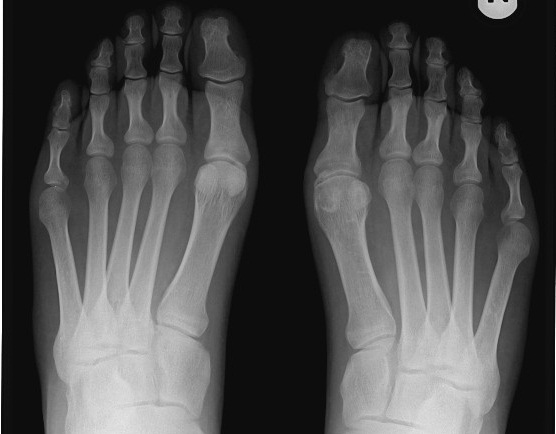

Pan Łukasz (nazwisko do wiadomości Redakcji) prowadzący spółkę cywilną, a zarazem jednoosobową działalność gospodarczą na terenie całego kraju, 22 grudnia ubiegłego roku złamał palec u lewej nogi. Lekarze z sądeckiego szpitala zaproponowali mu przeprowadzenie operacji, której chciał uniknąć. Dlatego postanowił leczyć się prywatnie i z własnych funduszy zapłacić za rehabilitację. Lekarz prowadzący stwierdził, że pan Łukasz nie jest zdolny do pracy i wystawił zwolnienie do 22 lutego.

– Przedwczoraj (12 lutego – przyp. Red.) udałem się do sądeckiego ZUS-u, bo otrzymałem wezwanie na komisję lekarską. To już drugi raz. Dwa lata temu byłem sprawdzany, gdy robiąc drzewo uszkodziłem sobie palec u lewej ręki. Lekarze nie dawali mi szans na uratowanie palca. Dzięki intensywnej rehabilitacji udało się.